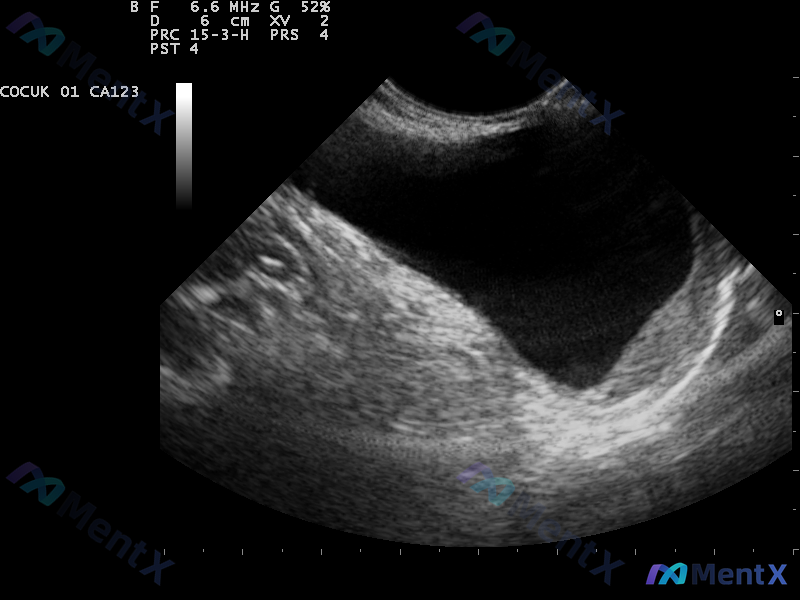

整理了一个儿科病例资料,有几个点比较值得讨论。 患者信息:5 岁男童 主诉:睾丸无痛肿胀 现病史:1 岁时首次发现肿胀,逐渐增大。无外伤手术史,无热带地区居住史,免疫接种正常。 体征: - 双侧睾丸肿胀,无压痛 - 波动感明显,透光试验阳性 - 仰卧时肿胀部分减轻 - 咳嗽冲动试验阴性 影像提示:超...